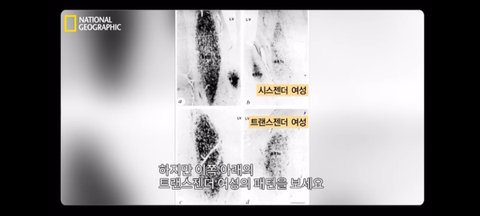

사진도 좀 봐줄래 과학적으로 입증 되었어

트랜스젠더는 존재해